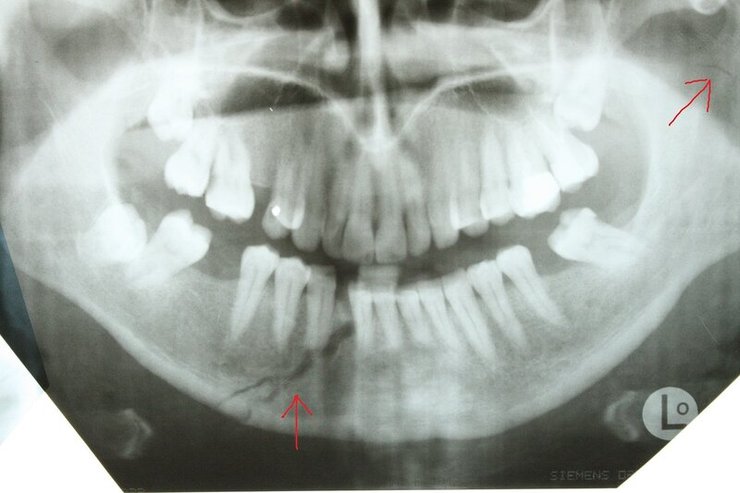

Сын главы Чечни Рамзана Кадырова Адам Кадыров мог сломать челюсть, когда попал в ДТП. Кроме этого, он имеет еще ряд менее значительных травм.

Авторы отмечают, что характерный для такой травмы отек лица спадает лишь через 1-2 недели. А на то, чтобы снять фиксацию челюсти, понадобится примерно месяц.

Челюсть Адама Кадырова NIYSO

Также в результате аварии у Кадырова-младшего могли появиться рваные раны, рассечения, разрывы кожи и гематомы. Из-за этого может понадобиться еще несколько недель, чтобы скрыть последствия аварии.